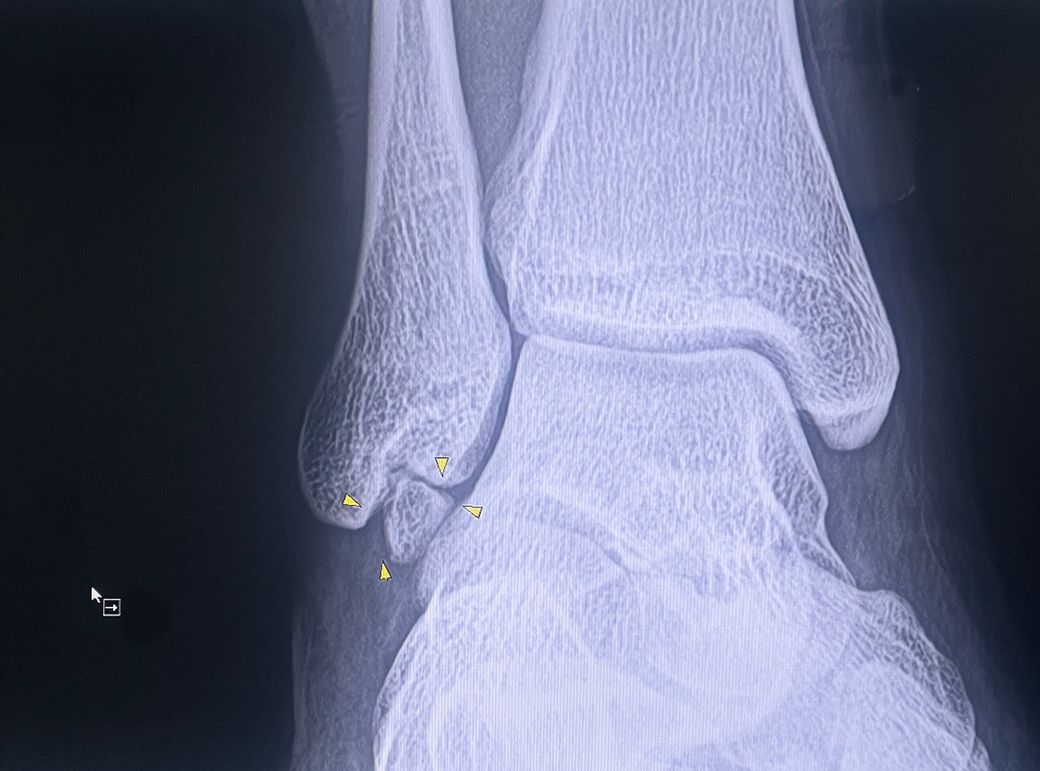

며칠 전 발목을 많이 접질러서 통증으로 인해 정형외과에 갔는데 표시되어 있는 뼈가 원래 있는 뼈가 아닌데 분할되어서 좀 크게 자리가 잡혀있고 저 뼈때문에 작은 충격에도 인대를 자극해 통증을 심하게 느끼는 거라고 하더라고요.. 그래서 딱히 개선을 할 방법이 없다고 말씀하셨는데 맞게 진료를 받은 건가 해서 여쭈어봅니다

사진과 설명상 부골(분리된 작은 뼈) 또는 붙지 않고 남은 작은 골조각 가능성이 높습니다. 이 뼈가 인대 근처를 계속 자극해서, 조금만 접질리거나 충격이 있어도 통증이 심해지는 상태로 보입니다. 위험한 종양이나 큰 병은 아니고, 흔히 있는 구조 문제입니다. 보통은 약·물리치료·보호대·깔창 같은 보존치료로 조절합니다. 다만 통증이 반복되거나 오래 지속되면 MRI로 인대 손상과 염증 여부를 확인해보는 게 좋고, 그래도 계속 힘들면 드물게 부골 제거 수술을 고려합니다. 크게 위험한 상태는 아니지만 통증이 계속되면 정밀검사 후 치료방향을 잡는게 가장 안전합니다. 빠른쾌유를 빕니다!

사진 위치상 "부주골(추가뼈) 또는 과거 인대 손상 후 생긴 골편" 가능성이 높아 보여요.

이런 뼈는 원래 타고나거나 예전 접질림 뒤에 남아 "인대 자극.통증 원인"이 될 수 있습니다.

네, 진단받으신 소견상에 크게 문제는 없는 것으로 생각되는데요, 발목관절을 형성하는 세개의 뼈 이외에 표시된 부분에 부골 혹은 이분 골절선으로 추정되는 구조가 있어 일반적인 발목관절과 달리 해당 변화가 발목 주변의인대나 연부조직을 자극하여 통증을 느끼게 되는 것으로 생각됩니다.